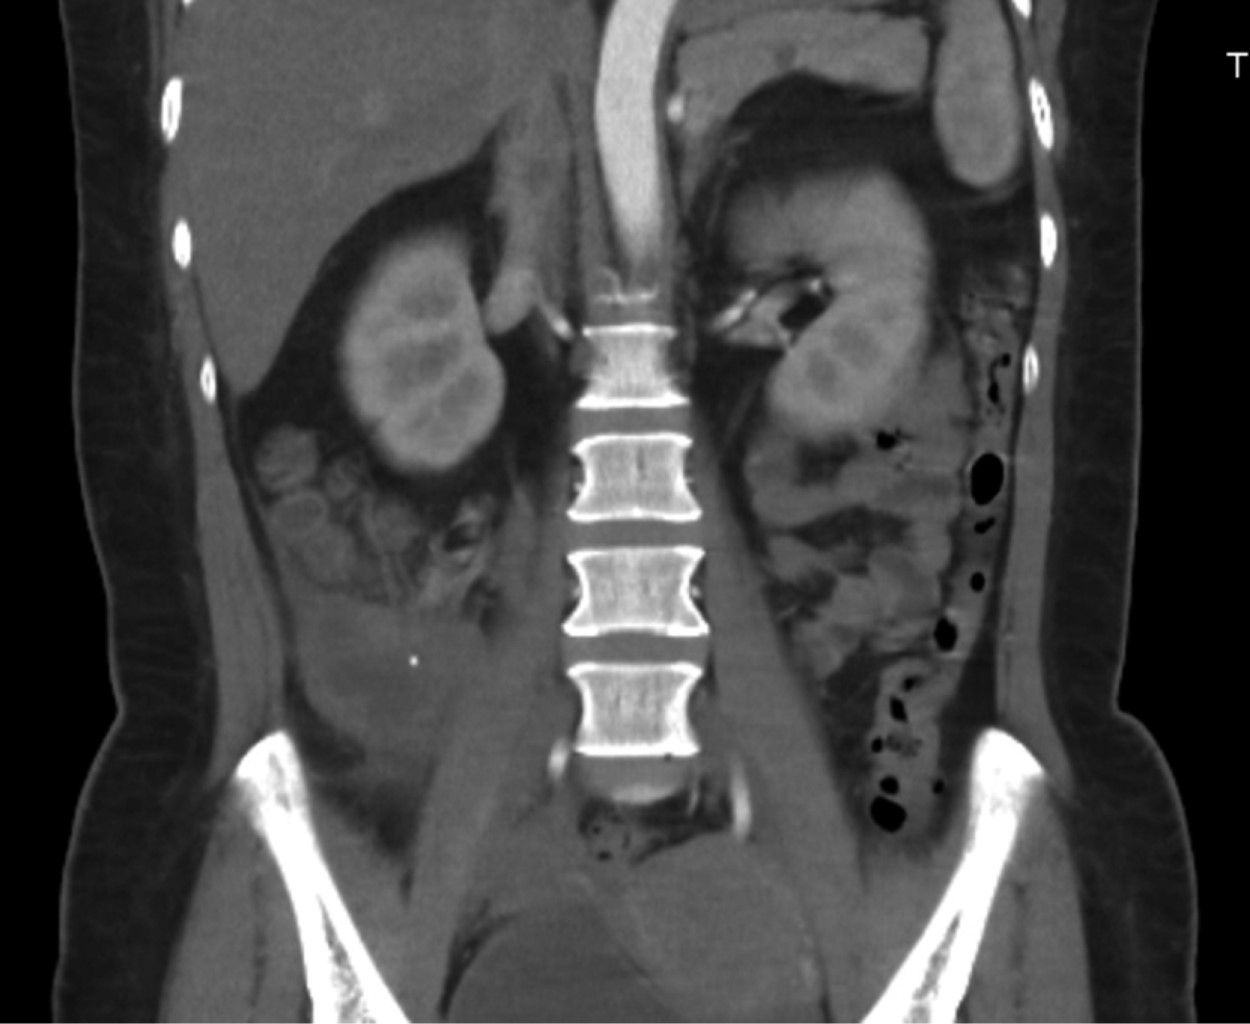

Tomografía simple y contrastada abdominopélvica 03/11/22: colección sub y retrocecal de 50 cm3 con proceso inflamatorio periférico, lo cual sugiere proceso apendicular complicado (Figuras 1 y 2).

Figura 1

Figura 2